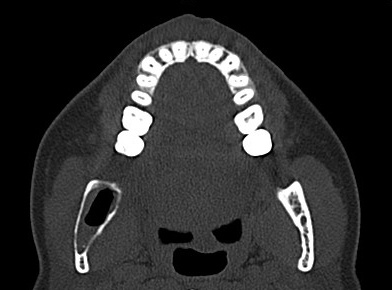

Ein ergänzend durchgeführtes Denta-CT des Unterkiefers (Abbildungen 2 und 3) zeigte eine zystische Raumforderung im Bereich der rechten Unterkieferhälfte, welche bis weit in den aufsteigenden rechten Unterkieferast reichte. Der Nervkanal des rechten N. mandibularis verlief durch die Raumforderung und ließ sich nicht sicher abgrenzen.

Die durch den zuweisenden Kollegen entnommene Probe erbrachte die Diagnose eines keratozystischen odontogenen Tumors. Die extraorale Untersuchung bei der stationären Aufnahme war unauffällig, der intraorale Befund ergab ein karies- und füllungsfreies Gebiss. Die ergänzend angefertigte Computertomographie des Unterkiefers zeigte eine von der Basis des Unterkiefercollums bis distal des Zahnes 44 reichende Zyste (Abbildungen 6 und 7).